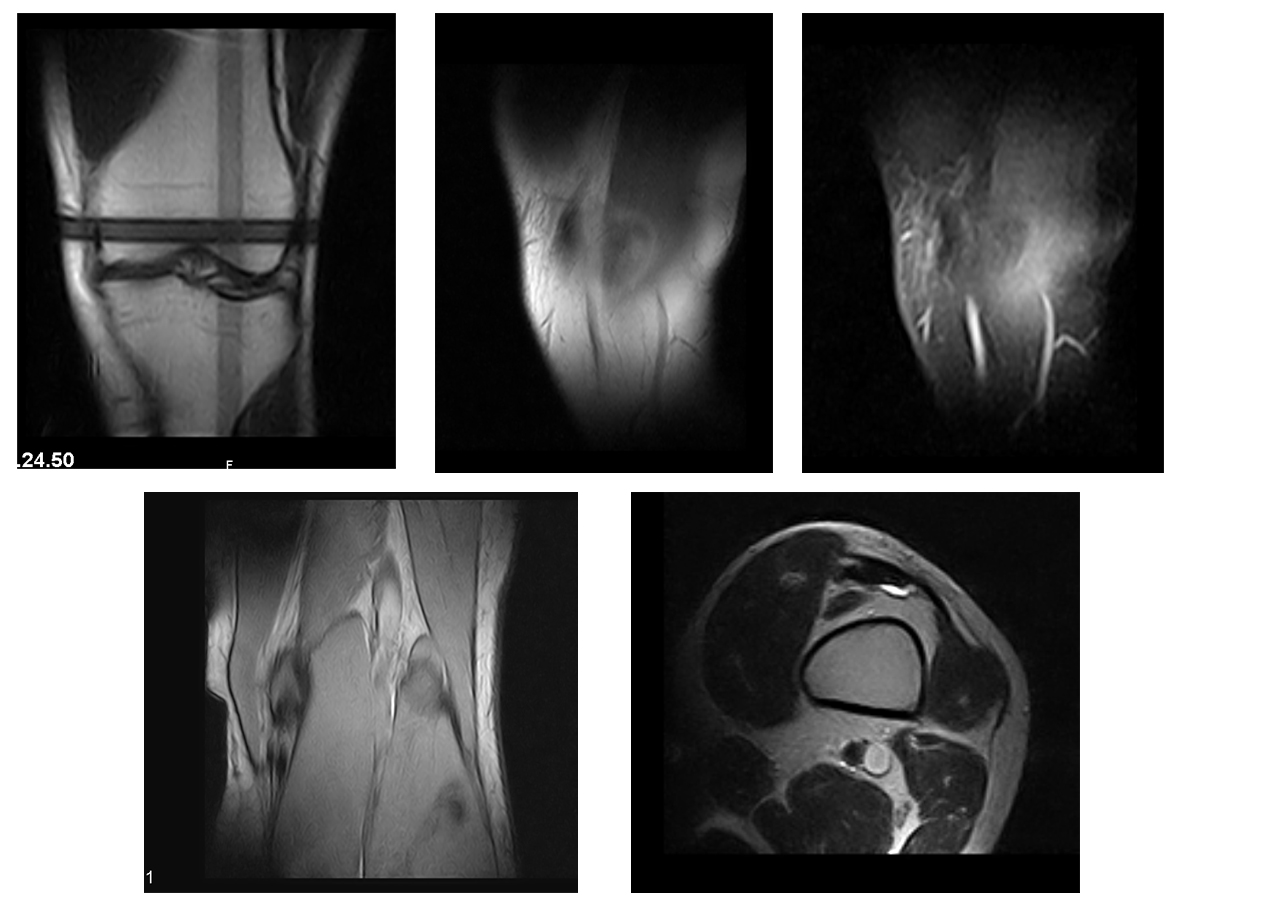

3 giorni fa ho fatto una RM dalla quale si attesa una DIASTASI LCL, ho cercato un pò su internet ma non ho trovato assolutamente cosa significhi e come devo comportarmi a riguardo, tenendo conto del fatto che sono uno sportivo e vorrei ricominciare al più presto la mia attività.

il reperto dice:

L'indagine eseguita con magnete permanente dedicato da 0.2 T secondo i piani assiale, coronale e sagittale

Non significativa falda di versamento endoarticolare.

Non evidenti alterazioni di segnale a carico dei menischi.

LCA, LCP regolari per calibro decorso e segnale.

Diastasi di LCL.

Non evidenti alterazioni di segnale a carico della spongiosa dei segmenti scheletrici esaminati.

Regolare il T. rotuleo e la porzione visualizzata del T. quadricipitale.

Allego alla discussione la mia RM e ringrazio di cuore chi vorrà rispondermi.

rm.jpg